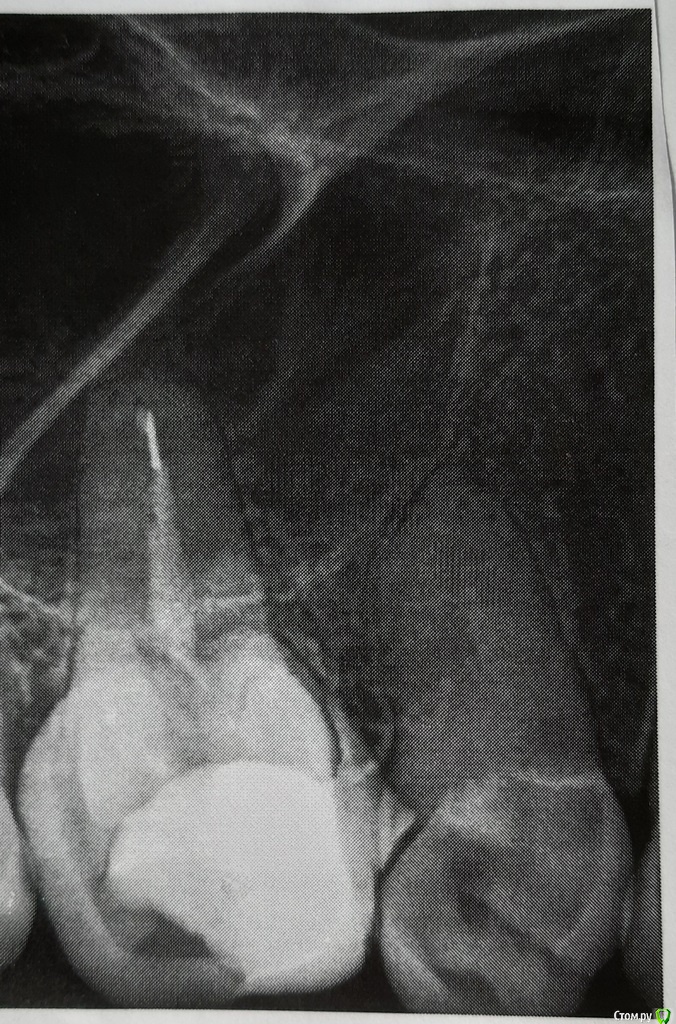

Анжела Ос Опубликовано 9 апреля, 2020 Поделиться Опубликовано 9 апреля, 2020 Уважаемые доктора! На снимке 2 зуба. Верхняя челюсть, правая сторона. Если считать от переднего, первого зуба: Пятый (на фото слева) и Четвёртый (на фото справа).Вопрос. Сперва стал беспокоить Пятый. Перестала его нагружать, прошёл. Если беречь и есть только мягкое, вообще не беспокоит. Один врач сказал, удалять, не затягивать, там киста и зубу кирдык. Другой врач сказал, нет никакой кисты и надо протезироваться.На днях заболел Четвёртый. Он ни разу не лечёный. На холодное и горячее последнее время реагировал очень болезненно. А тут появилось распирание, лёгкая пульсация и боль при касании даже языком. Щека чуть припухла. Врач предложил вскрыть, не умер ли там нерв. Но я не рискнула наугад вскрывать зуб, здоровый с виду. Может, это отдаёт из Пятого зуба? Тогда вскрытие будет неоправданным. Сегодня Четвёртый перестал реагировать на горячее. Болеть тоже почти перестал, если не нагружать. Припухлость и воспаление остаются прежними. Десна в этом районе сильно оголена уже давно.Что с этими двумя зубами делать? Спасибо всем за советы! Ссылка на комментарий

red_butler Опубликовано 9 апреля, 2020 Поделиться Опубликовано 9 апреля, 2020 Шестой и пятый перелечить и под коронки. И сделайте снимок четвёртого 1 Ссылка на комментарий